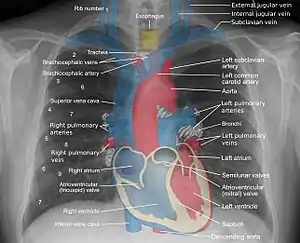

![]() Mediastinum anatomy. ![]() Some mediastinal structures on a chest radiograph.